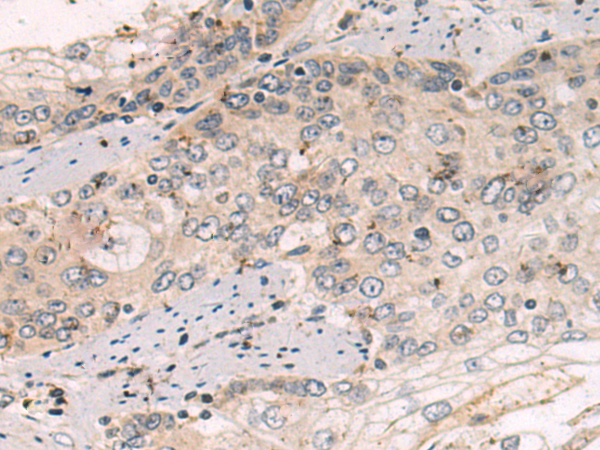

分类: 科研抗体货号: P10609别名: TRAP; CATC4; PCTAIRE2BP应用: IHC反应种属: Human, Mouse, Rat